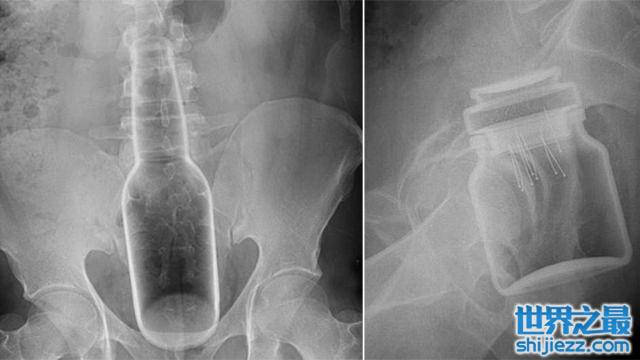

而据美国消费者安全委员会的数据表示,直肠是最多人把异物收纳进去的地方。像是啤酒罐、圣诞节挂饰、药瓶、雪茄管,甚至是一整尊的巴斯光年。这些都曾经是急诊室的医生,从病患的屁屁里面拿出来的诡异物品。